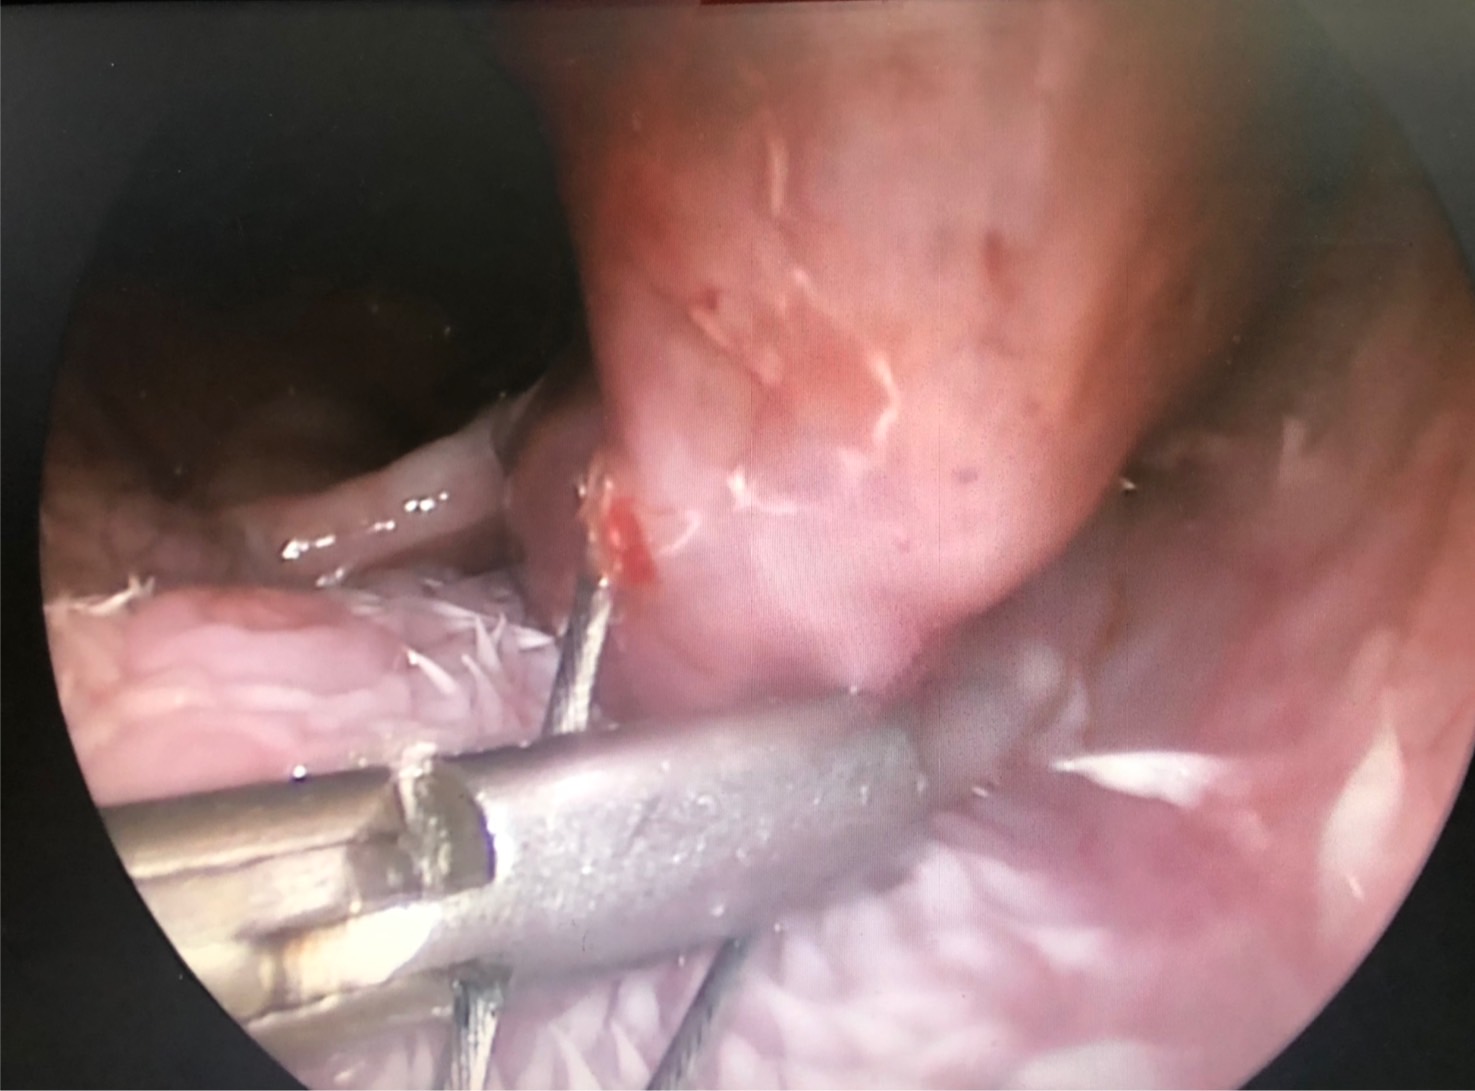

初步懷疑呼吸道阻塞,安排電腦斷層掃描/內視鏡探查手術,精準定位病灶團塊的範圍,

利用內視鏡輔助套環套住團塊後經電燒將可見到範圍盡量切除乾淨。

同時將切除的團塊做病理切片。術後三個月到現在沒有症狀也沒有復發。